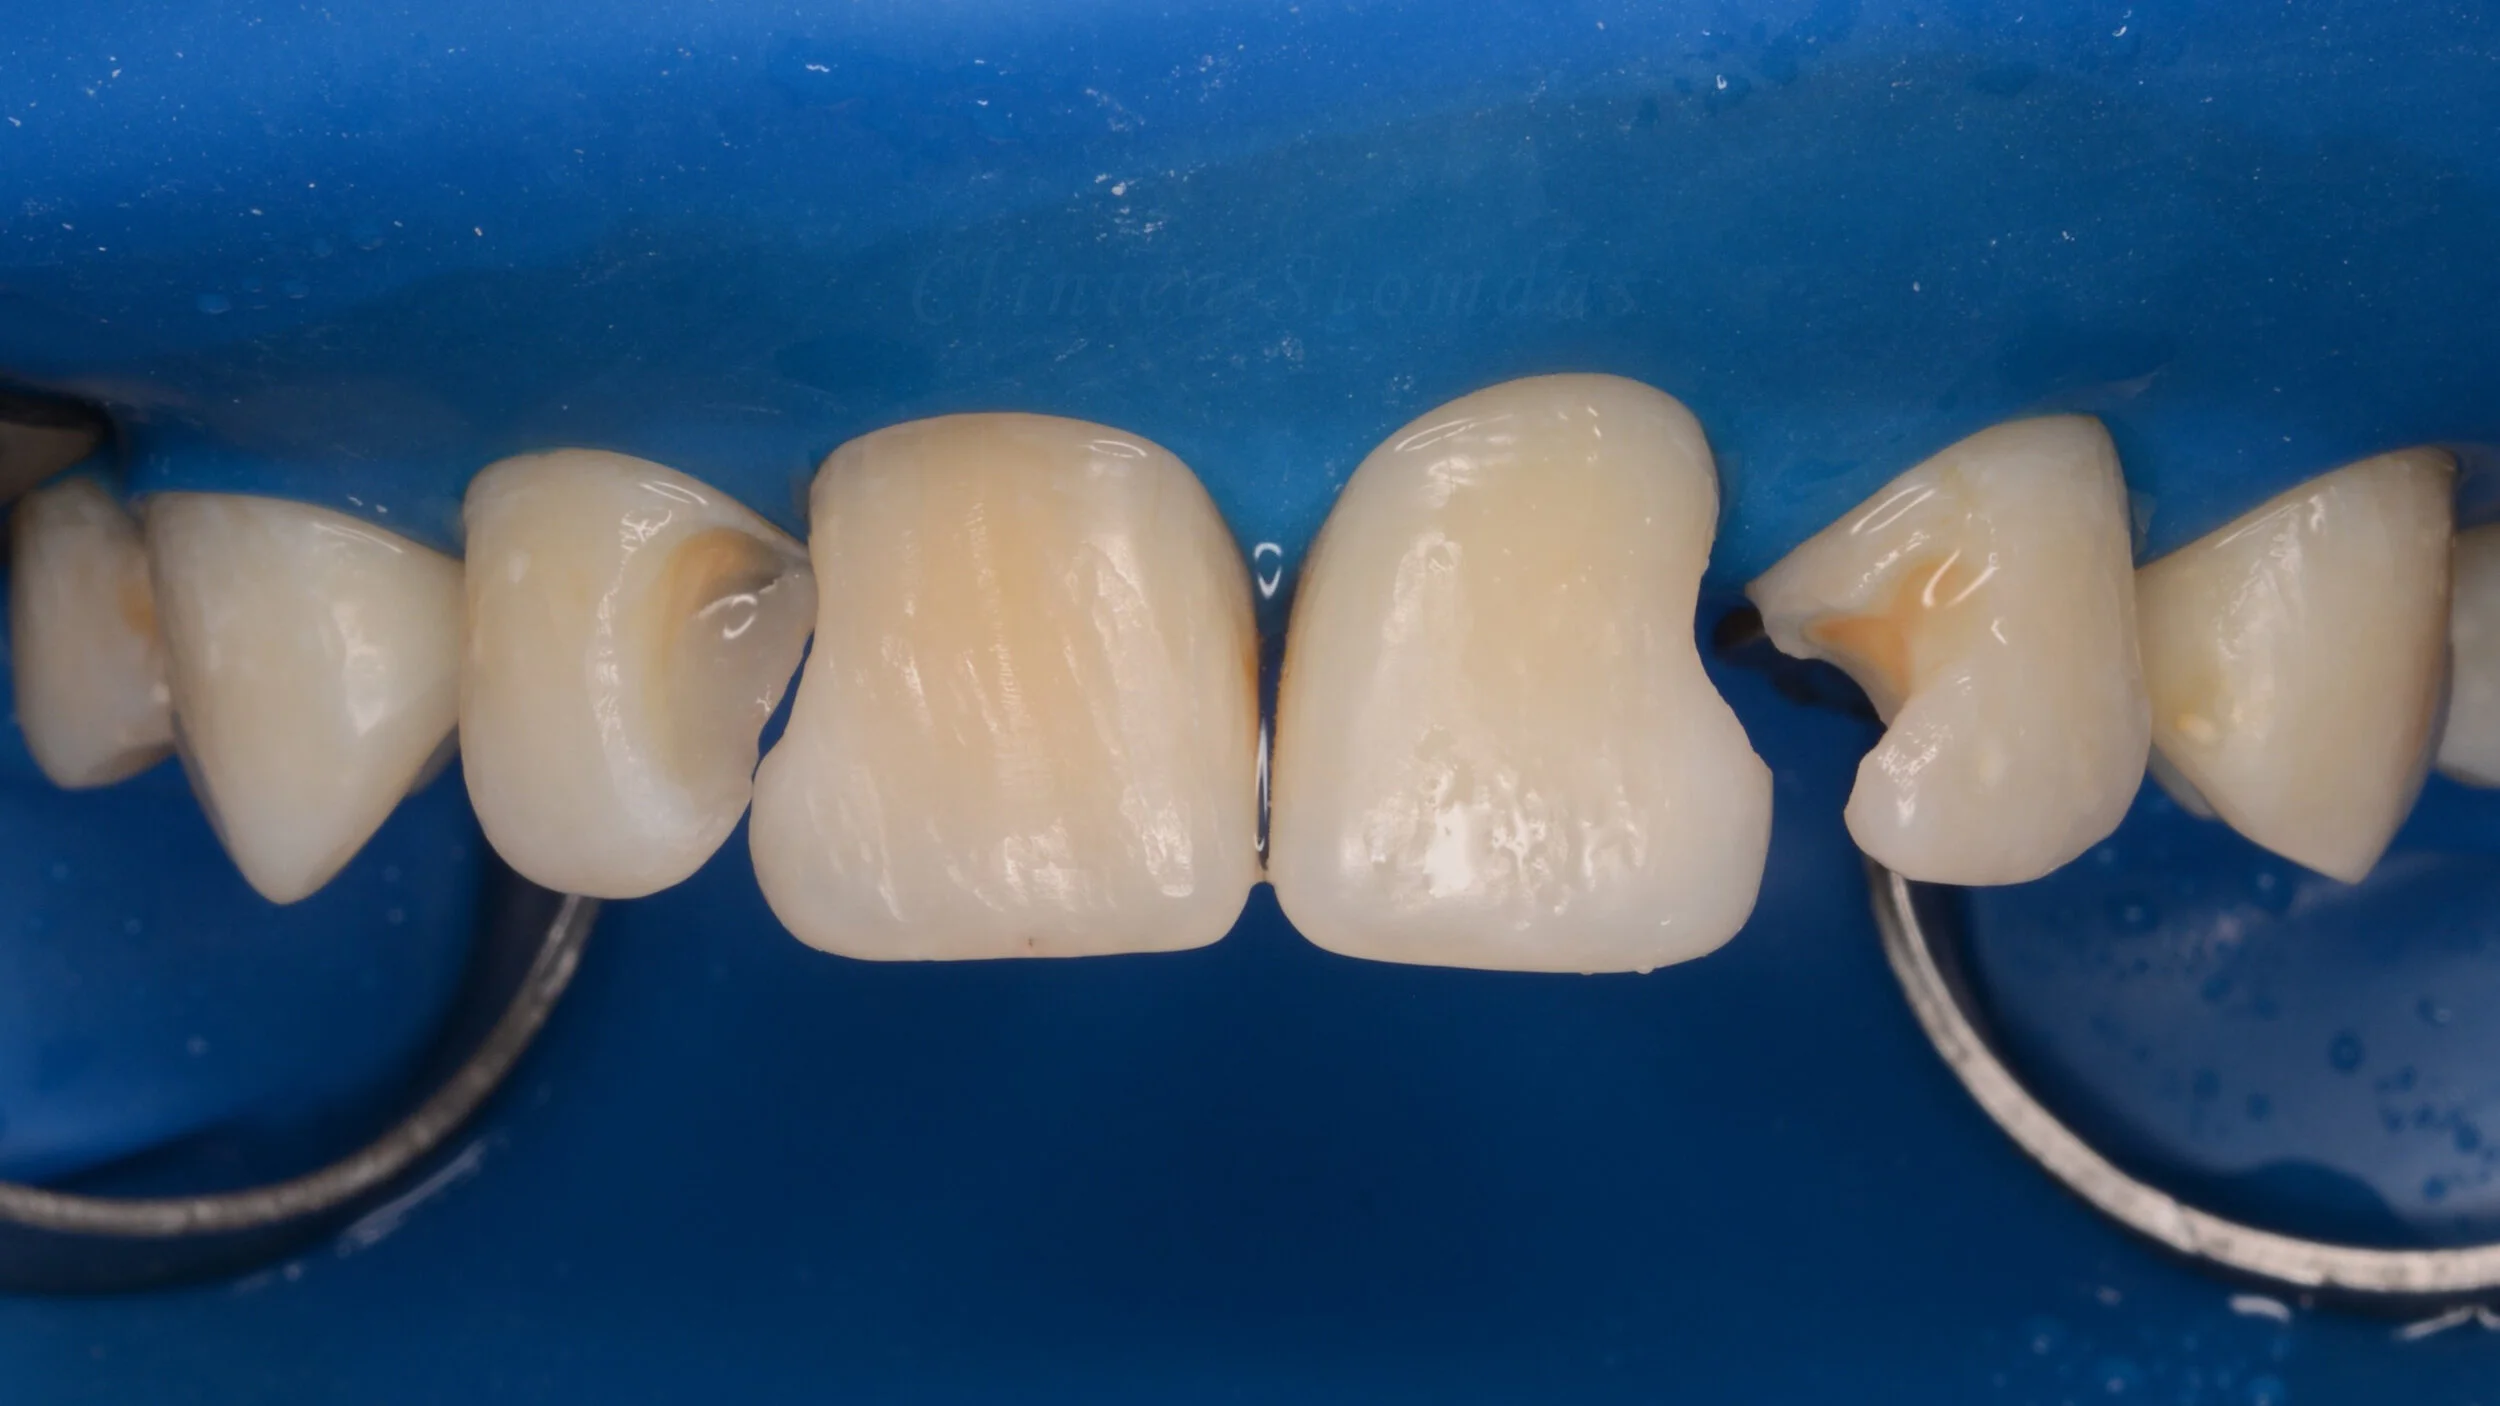

3. Diga ajuta foarte mult si la anumite procedee din protetica dentara si anume la amprenta optica (cu scanner intraoral) sau la cimentarea coroanelor / fatetelor, inlay-urilor sau onlay-urilor integral ceramice, unde mediul uscat este obligatoriu pentru retentia viitoarei restaurari.

3 izolare cu diga cimentare S.jpg